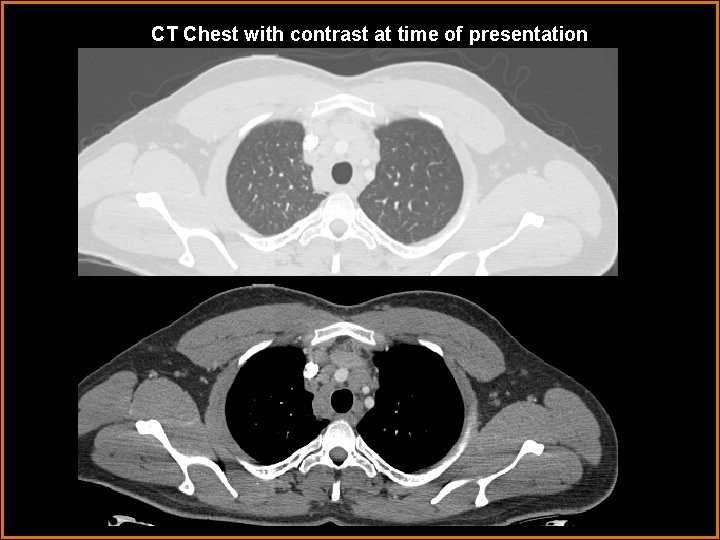

CT Chest with contrast at time of presentation

Findings and Differentials Findings: Chest x ray demonstrates development of new bilateral hilar masses and scattered small nodules in both lungs. CT Chest demonstrates multiple small nodules in a perilymphatic distribution with upper lobe predilection. Multifocal patchy ground glass airspace opacities involving mid and upper lungs. Bronchovascular interstitial thickening. Bilateral symmetric hilar and mediastinal adenopathy. Differentials: • Sarcoidosis • Lymphangitic spread of tumor with malignant lymphadenopathy